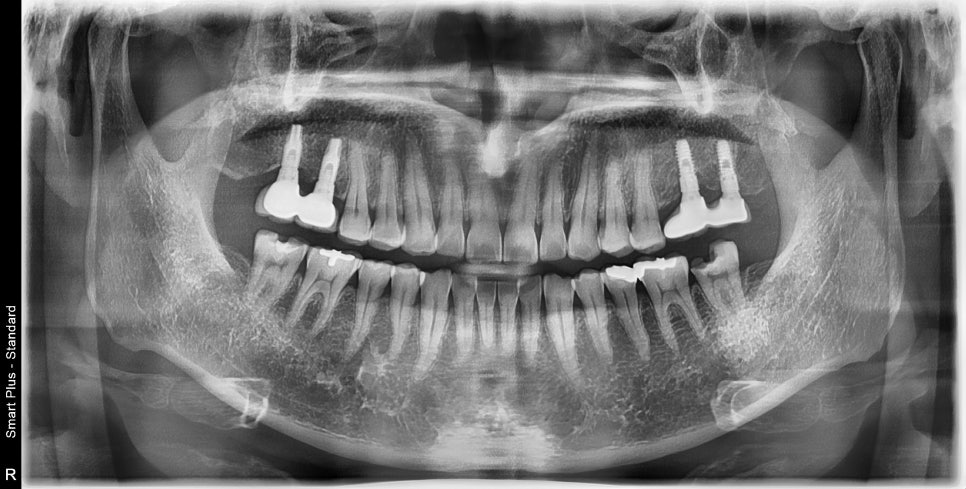

과거에 때웠던 치아에 약한 재료가 파절되면서

그 안쪽으로 충치가 진행되면서 신경관 입구가 노출되며 MTA 적용 후 레진 보강 후

크라운치료로 같은 과정으로 치료가 마무리된 케이스입니다.